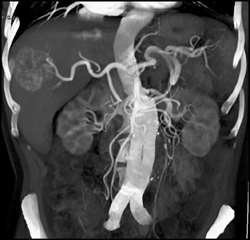

Hepatoma